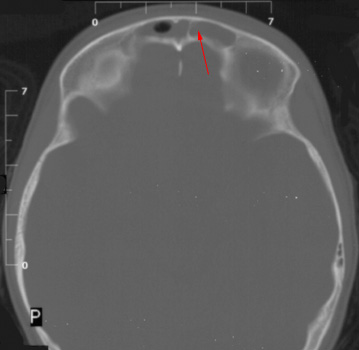

On CT, an epidural abscess appears as a focal low-density epidural mass. Dural enhancement may be present as well. The mass may extend into the subgaleal space. It also may cross the midline but usually does not cross suture lines.

![]() ![]() In the left image

notice the rim enhancing epdural fluid collection (arrowheads). In the